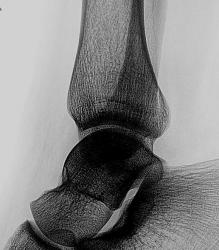

Отличные, высокоструктурные снимки - честь Вам и Вашим помощникам - лаборантам. Сначала тоже сильно засомневался, ибо линия перелома (смещения то нет) "накладывается" на задний контур м/берцовой кости, но нижний снимок убедил, что перелом "задней" лодыжки.

Валентин Львович, я ни стал мучить пациента и делать в косой проекции, но на будущее я обязательно учту, сопоставив кническую и рентген-картину(если внимательно поглядеть то линия перелома не совсем наклалывается на край м/берцовой кости, а так же четко визуализируемую структуру костных балок, которые четко видно на цифре), было выставлено заключение о переломе.

Ребяты! Всё тут видно. Но можно лучше. Ставим в браузере масштаб не 100%, а 200% или 300% и видим (даже без очков!) – линия перелома б. берцовой позади проекции контура м. берцовой и направления их книзу расходятся.

По представленному случаю. Имеется изолированный перелом заднего края большеберцовой кости без смещения костных отломков. Кстати, редко встречаются изолированные. Чаще в сочетании с переломами лодыжек, вывихом таранной кости.